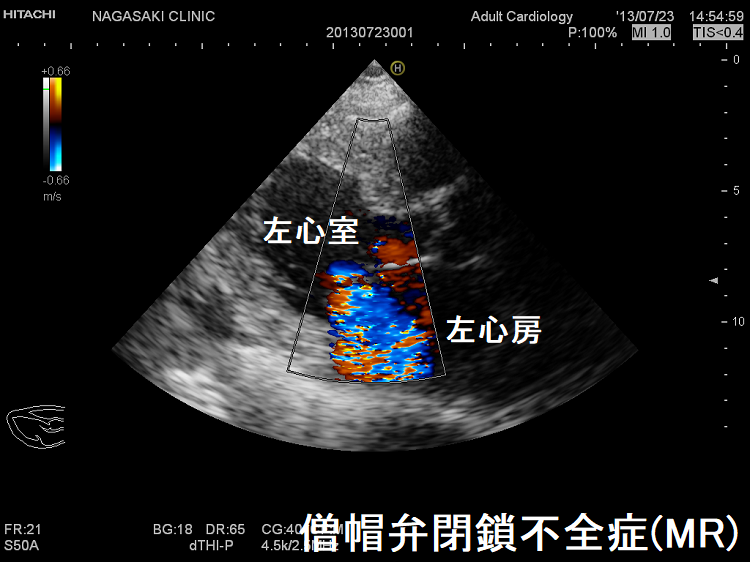

僧帽弁閉鎖不全症(MR)は、

- 僧帽弁破壊:動脈硬化、リウマチ熱による僧帽弁の石灰化、感染性心内膜炎

- 僧帽弁逸脱:閉塞性肥大型心筋症、甲状腺機能亢進症の30%に起こる

甲状腺機能亢進症/バセドウ病、甲状腺機能低下症/橋本病(下記)

などが原因となります。

甲状腺機能亢進症/バセドウ病、甲状腺機能低下症/橋本病では僧帽弁腱索/乳頭筋断裂の頻度が高い(Endocr Rev. 2005;26(5):704–728.)。

自己免疫性に粘液多糖類が蓄積し、僧帽弁の粘液水腫性変化が生じます

- 甲状腺機能亢進症/バセドウ病の33%

- 甲状腺機能低下症/橋本病の36%

(Thyroid. 2002 Mar; 12(3):193-5.)

特に循環血液量・心拍出量が増加する甲状腺機能亢進症/バセドウ病では、僧帽弁腱索/乳頭筋断裂を引きおこす危険性が高い。(J Endocr Soc. 2018 Sep 17;2(11):1246-1250.)[Endocrinol Diabetes Metab Case Rep. 2022 Jul 1;2022:22-0298.]

僧帽弁腱索/乳頭筋断裂がなく、粘液腫性変性による中等度から重度の僧帽弁閉鎖不全症(MR)なら、甲状腺機能の正常化に伴い改善する可能性があります。[BMJ Case Rep. 2021 Feb 4;14(2):e239626.]